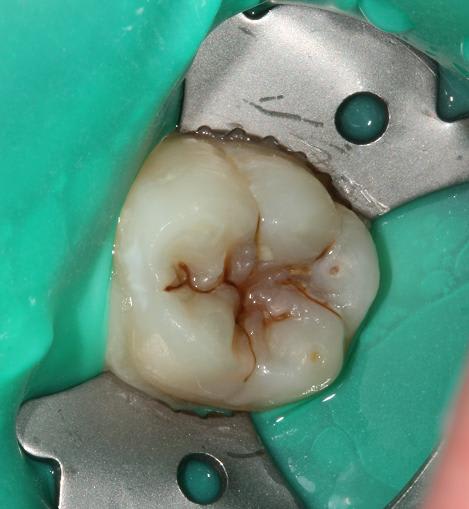

Quelques photos pour illustrer le sujet initial. Dommage que ces dents n'aient jamais eu de sealants.

Pour l'effraction pulpaire sur dent asymptomatique, je fais le protocole que Choixpeau avait mis sur le forum : hypochlorite puis adhésif directement au contact. Aucun problème à court terme pour le moment.

Si effraction plus importante : MTA.